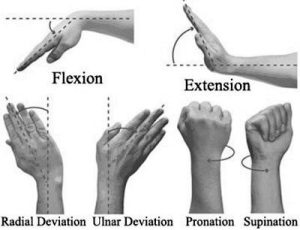

- در هفته ۶ تمرینات فعال چرخش ساعد ( pronation/supination ) در دامنه بدون درد آغاز می شود.

- از هفته ۸ به بعد تمرینات فعال و غیرفعال دامنه حرکتی مچ دست در تمام جهات شروع می شود.

- حرکات خم شدن ( flexion) ، باز شدن( extension) ، انحراف به سمت اولنا ( Ulnar devation) ، انحراف به سمت رادیال (radial devation ) و چرخش ساعد pronation/supination) ) که در شکل ۴ نشان داده شده است،با استفاده از دمبل یا باند الاستیکی قابل انجام است.

شکل ۴. حرکات مچ دست